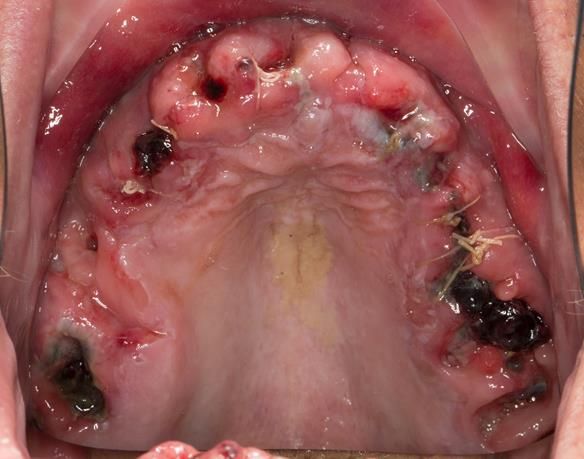

- The remaining maxillary teeth had hopeless prognosis in the short term. They exhibited 80 - 100% alveolar bone loss with increased mobility (Grade 2 - 3).

- Extraction of all upper teeth and LR5 and LL4 and fitting of immediate acrylic based (Mk 1) dentures - complete upper and lower partial

The clinical situation and treatment process is shown in detail below with photographs.